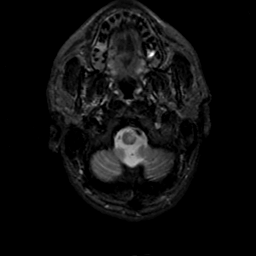

MR Study #19, August 25, 1991 -- Slice #3

[Home][Help][Clinical][Tour 1][Tour 2] Slice 3